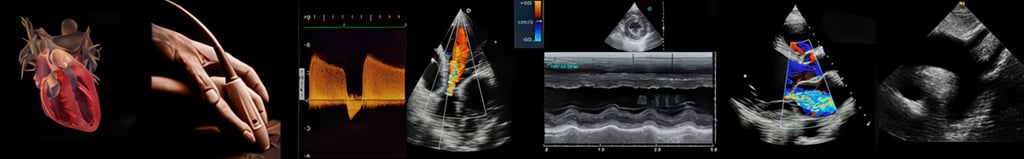

Hands-On Cardiac Ultrasound Imaging & Doppler

Adult Echocardiography

Echocardiography is not just another imaging modality—it's a dynamic, physiologic tool that informs assessment of function, hemodynamics, and real-time clinical response. This hands-on cardiac course matters because it teaches you to acquire meaningful views under real conditions, interpret Doppler and motion patterns with purpose, and integrate those findings into urgent and routine cardiovascular decision-making. You walk away with competence you can use immediately at the bedside, not just a stack of saved clips.

What You'll Be Able to Do Clinically.

By the end of this hands-on cardiac ultrasound course, you will be able to:

Acquire all standard cardiac imaging views reliably, with purposeful probe positioning and patient optimization

Navigate cardiac anatomy in motion, understanding how structure, timing, and physiology interact in real time

Apply Doppler techniques intentionally to assess flow, pressure relationships, and hemodynamics rather than relying on presets

Evaluate ventricular function, chamber size, wall motion, and loading conditions with clinical context

Assess valvular anatomy and function using image-based reasoning instead of rote measurements

Recognize common and critical cardiac findings and distinguish normal variants from pathology

Integrate cardiac ultrasound findings into bedside decision-making with clarity and confidence